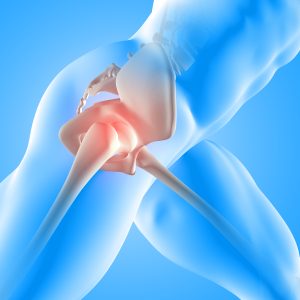

Most of the time we focus on the bigger muscle groups, which eventually take over and cause all sorts of problems with the rest of the kinetic chain. Start with the smaller, internal stabilizers; get those muscle on board first and then look to the outer. What ever sport you are involved in, these programs will help link the kinetic chain together properly, allow you to perform at you optimal without injury.